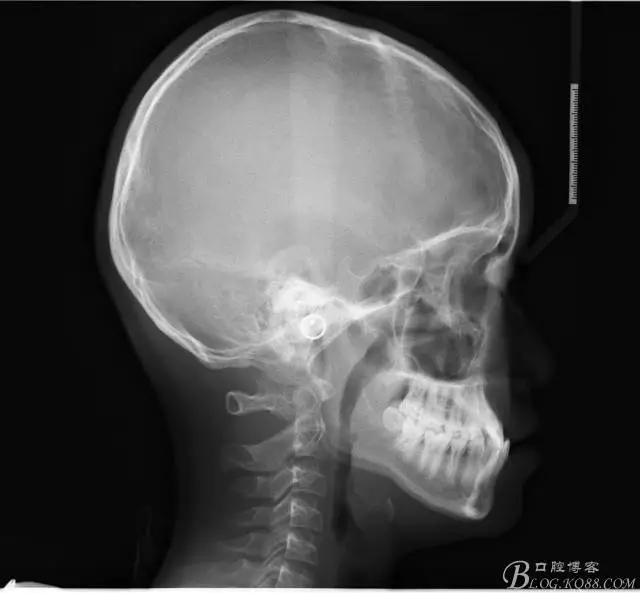

前牙反合伴擁擠的案例

通常情況下,前牙反合的患者因上頜發(fā)育不足,會(huì)伴發(fā)上頜前牙區(qū)牙列擁擠;

患者13歲,男性,自覺(jué)牙齒不齊要求矯正;